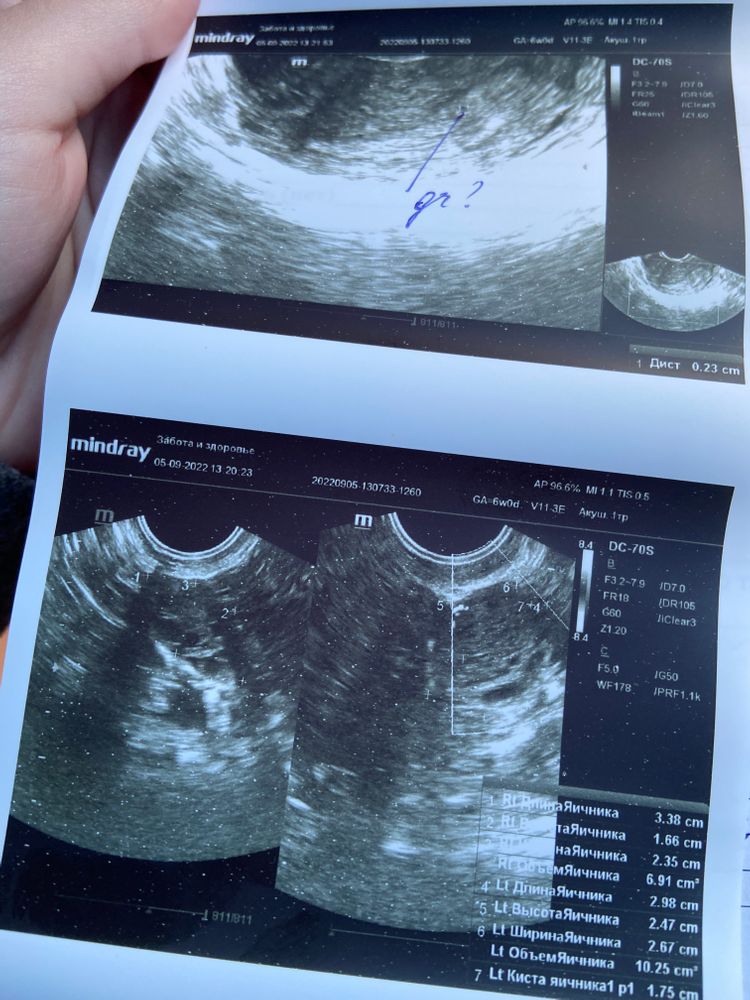

Сходила сегодня на УЗИ, до этого была в четверг(01.09), но там было ничего не видно и мне сказали прийти в понедельник(05.09). 3го числа сдала хгч, результат был 158, о беременности узнала 29.08 по слабой полоске на тесте.

Сегодня сдала ХГЧ и пришла на УЗИ. Вот что непонятно: врач увидела в матке только плодный мешок без плодного яйца.. Это вообще как, реально? Врач напугала внематочной беременностью, мол плодный мешочек может быть в матке, а ПЯ вообще в трубе.. Я в замешательстве, очень переживаю, не знаю что делать. Может у кого-то так было? Снимки узи прикрепляю

У вас нашли плодное яйцо без желточного мешочка. Какой размер пя точно не видно на фото.

Аня, нет, у девушки совершенно другая ситуация. У нее видели жёлтое тело в яичнике. У вас судя по протоколу и снимку УЗИ - в матке плодное яйцо. Пока пустое - что с вашим хгч - норма

А что там может быть видно если Диаметр плодного Яйца всего 2.1 мм.????!!! Что то ваш врач заговорился, кадеться он сам не понял что написал. Сдайте хгч в динамике, а если переживаете то через неделю к другому врачу на узи сходите. Но на узи нечего делать при хгч меньше 1000. А эмбрион видет при хгч больше 10000 обычно